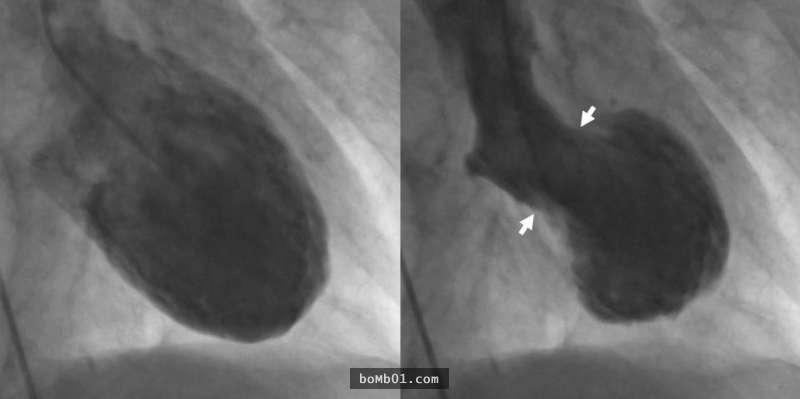

▼心碎症候群是日本在1990年代才確定的病徵,由於患者碰上劇烈的變故時,心臟會突然收縮變形,樣貌很像日本的「章魚壺」(takotsubo),所以也有這個別稱。